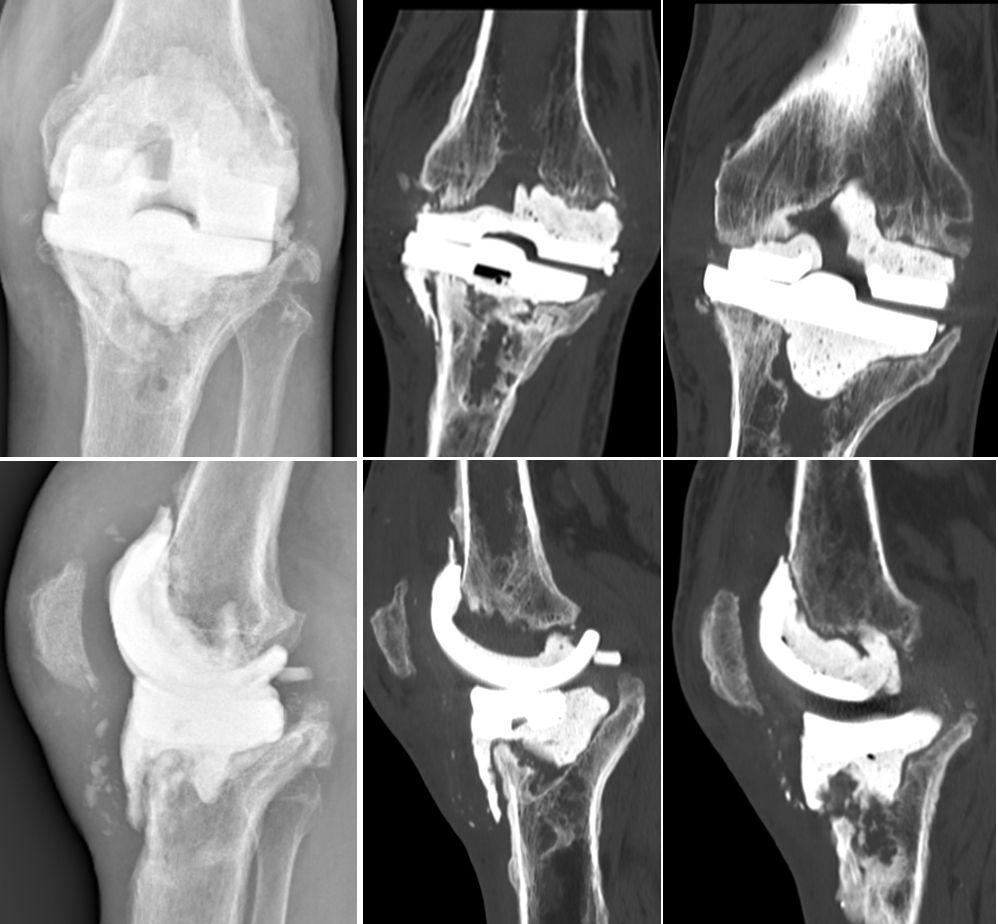

A few days before surgery, the surgeon and nurse can "implant" the real prosthesis and perform the upcoming procedure (fig. 6-8) using real instrumentation on the newly produced 3D model to determine the size of the components (fig. 9) and the need for wedges or cones, if necessary, to restore the correct position and rotation of the joint axis.

During implantation all the different options for stem length and offset, spacers, blocks and sizes can be preselected and every feature of the implant is already known and can be assembled. In many cases the preop plan fits very well with the final intraoperative solution (fig. 10-12).

The 3D model accurately reproduces all the bony landmarks that will be used for surgery and can be cut and manipulated with the surgical instruments. The model can then be sterilised, marked and taken into the operating room to help orient the surgeon and placing the components. The advantage of 3D printed models is demonstrated by bone loss after infection with Case 1 (Figs. 13 and 14) and after aseptic loosing with Case 2 (Figs 15 and 16).

Case 3 further demonstrates the advantages of 3D models for a 77 years old woman after two stage revision for septic loosening of a cemented primary implant 12 years ago. After reinfection and several AB spacers, bone stock on both femoral and tibial sides was compromised (see also fig. 1). Re-Revision surgery was planned with RHK using cones for both the tibia and femur (Figs 18 and 20).